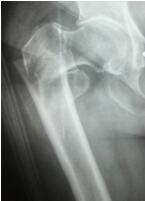

隨著我國人口老齡化加重,老年髖部骨折的病人也在逐年增加。據(jù)了解,高齡髖部骨折具有并發(fā)癥多、死亡率高的特點(diǎn),國際上對于高齡老人髖部骨折治療方式首選手術(shù)治療,并且要求手術(shù)在傷后48小時(shí)內(nèi)完成,越快越好。瀘州市中醫(yī)院通過多科協(xié)作,為髖部骨折的老年患者開啟快速就醫(yī)、快速檢查、快速手術(shù)、快速康復(fù)的綠色通道,成...